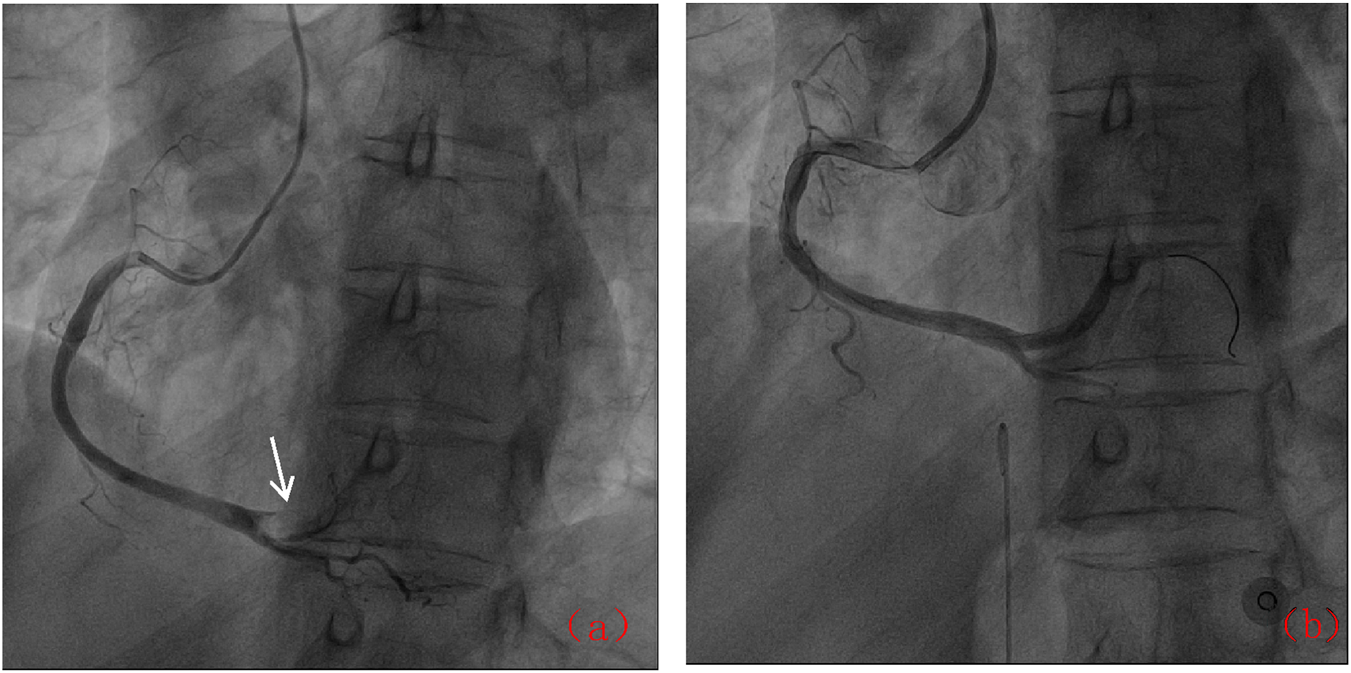

Following admission, the patient was administered avatrombopag 20 mg once daily and intravenous dexamethasone sodium phosphate 20 mg once daily to elevate platelet levels (aspirin was not co-administered due to positive urinary occult blood). A 40 mg daily dose of omeprazole injection was administered to prevent acute gastric mucosal lesions. A single therapeutic unit of apheresis platelets was transfused. On 12 December 2024, the platelet count was reassessed and found to be 122 × 109/L. Later that day, the patient developed chest pain. Electrocardiography revealed sinus bradycardia and ST-T changes, with ST-segment elevation of 0.05–0.10 mV in leads II, III, aVF, and V7-9, and biphasic T waves in V2-3 (Figure 1). Laboratory tests showed elevated myocardial markers: Myoglobin (MYO): 295 ng/mL (reference range: <50 ng/mL), Cardiac Troponin I (cTnI): 4.47 ng/mL (reference range: <0.1 ng/mL), NT-proBNP: 627 pg/mL (reference range: <900 pg/mL), and Creatine Kinase-Myocardial Band (CK-MB): 4.28 ng/mL (reference range: <5 ng/mL). Emergency coronary angiography revealed acute occlusion at the origin of the left ventricular posterior branch (Figure 2). A large thrombus was aspirated from the coronary artery, and subsequent angiography showed no fixed stenosis in the left ventricular posterior branch, indicating coronary artery thrombosis. Postoperatively, the patient was treated with dual antiplatelet therapy consisting of aspirin enteric-coated tablets (100 mg nightly) and ticagrelor (90 mg twice daily). Additional therapies included atorvastatin calcium tablets (20 mg nightly) for lipid lowering, pantoprazole sodium tablets (40 mg once daily) for gastric mucosal protection, low-molecular-weight heparin (6000 IU subcutaneously every 12 h) for anticoagulation. Her chest pain resolved completely by the second postoperative day. Her history included the use of avatrombopag in combination with aspirin without thrombotic events. In this hospitalization, aspirin was withheld due to occult bleeding. Coronary thrombosis occurred after 4 days of avatrombopag administration. The strikingly rapid onset of AMI (5 days post-avatrombopag initiation) coincided precisely with the peak platelet rise, reinforcing a direct link. Following consultation with hematology specialists, coronary artery thrombosis was considered potentially related to avatrombopag use. Discontinuation of avatrombopag was recommended, and dual antiplatelet therapy with aspirin enteric-coated tablets and ticagrelor was continued, with close monitoring of platelet count. On 17 December 2024, platelet count was 310 × 109/L, cTnI was 6.53 ng/mL, and NT-proBNP was 1,708 pg/mL. Fourteen days after discharge, the outpatient platelet count was 18 × 109/L. Aspirin and ticagrelor were discontinued, and the oral administration of 20 mg once daily of avatrombopag and 100 mg nightly of aspirin was resumed. As of the latest follow-up, no further thrombosis events have occurred.

FIGURE 2

Coronary angiographic results: (a) Acute occlusion of the posterior left ventricular branch (arrow); (b) Post-thrombus aspiration showing restored flow.